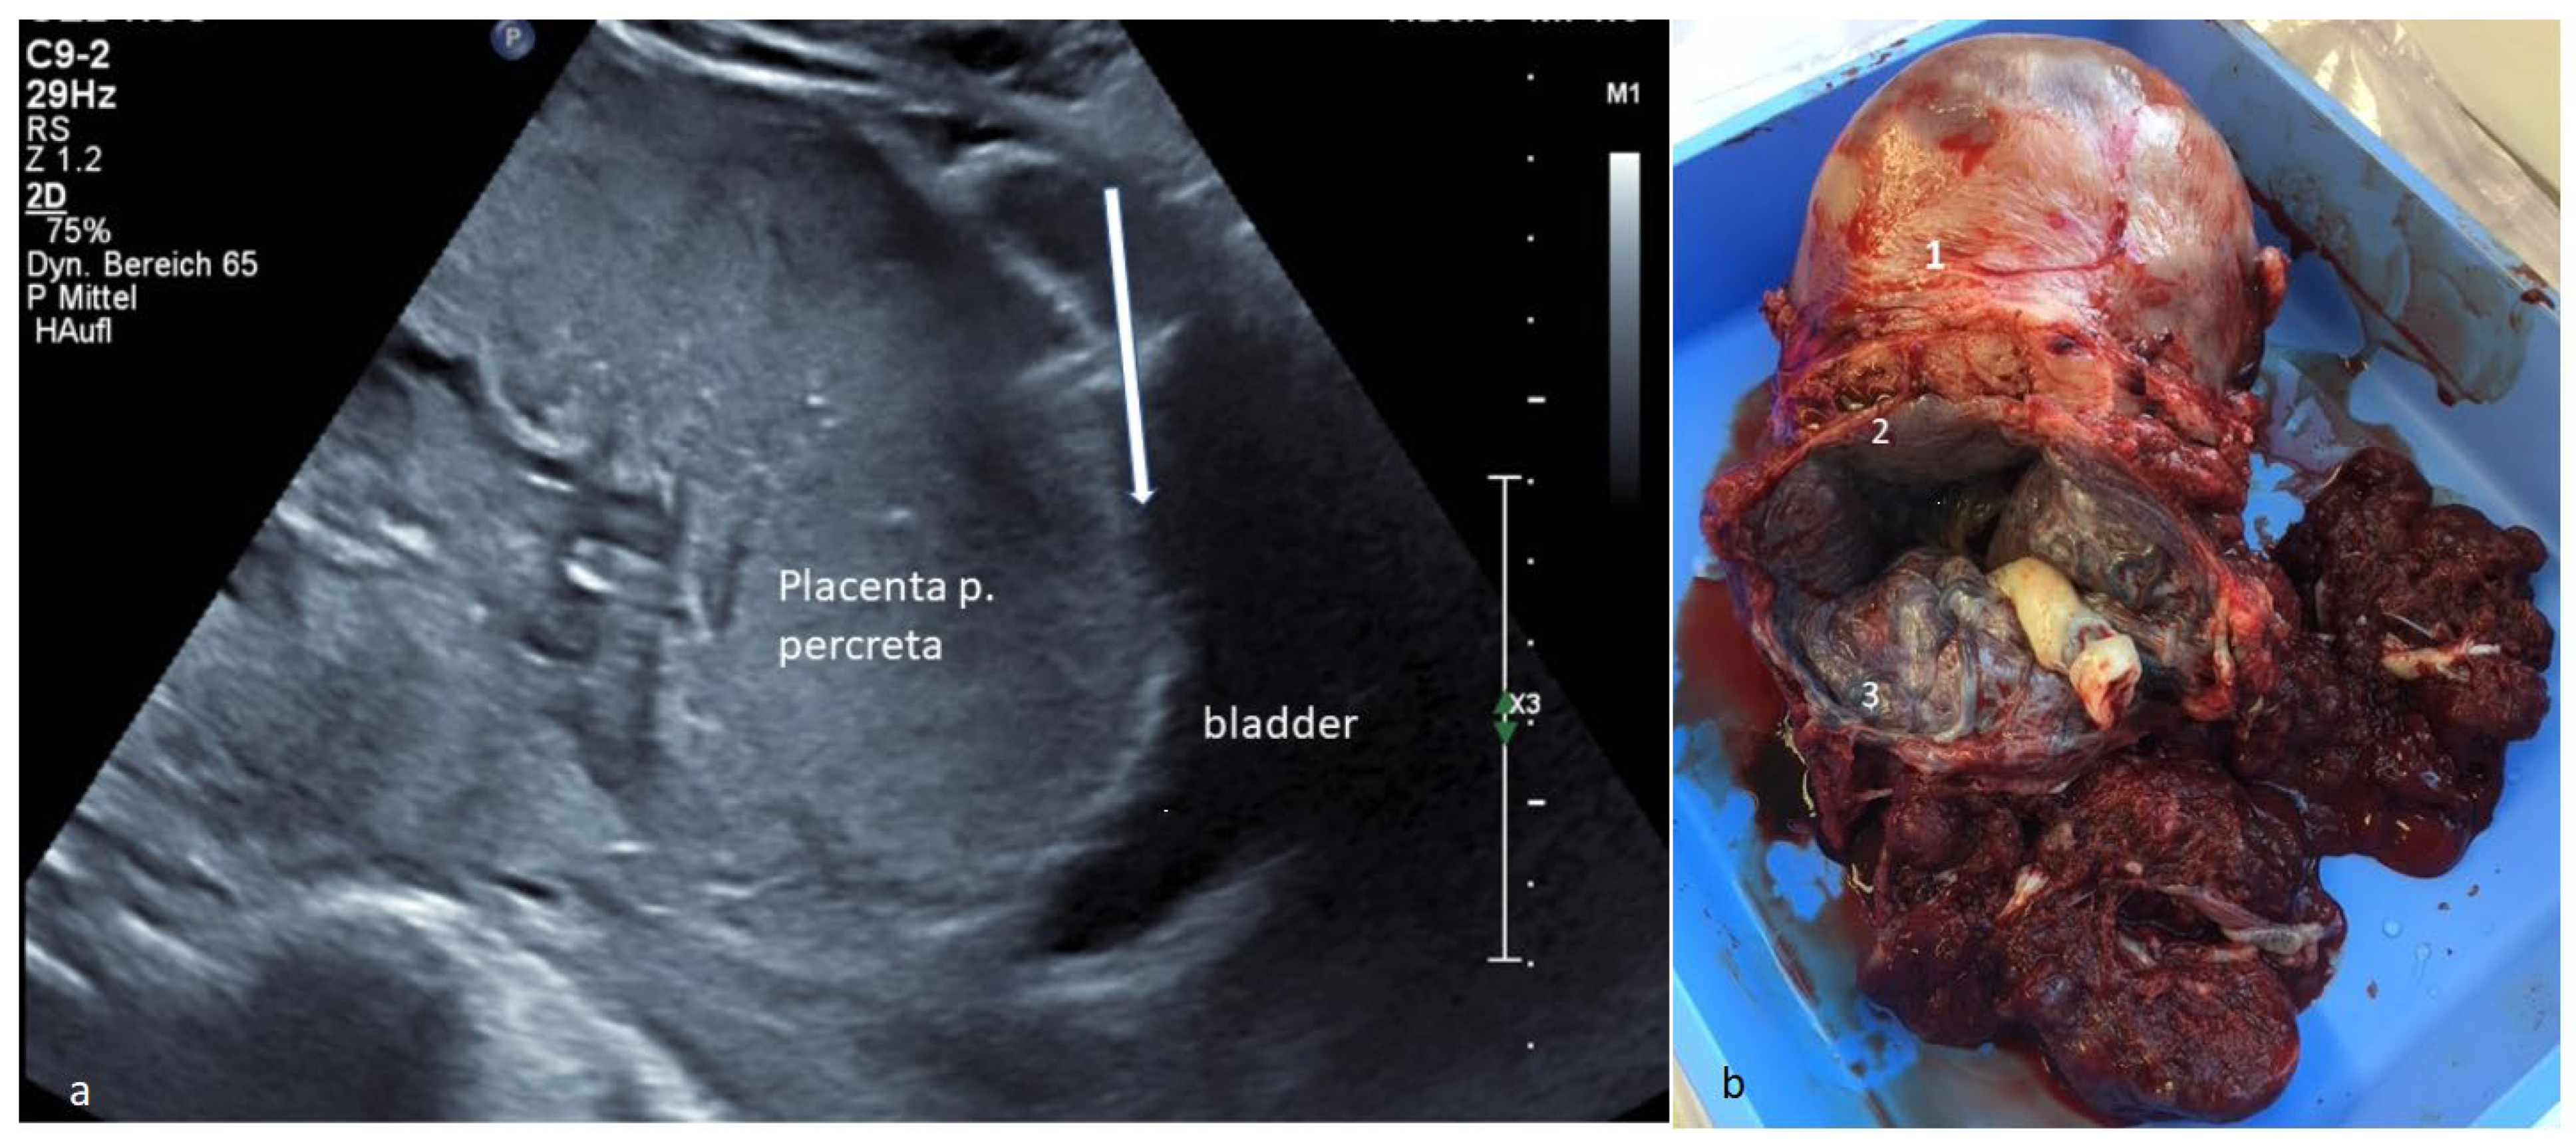

(a) Transvaginal ultrasound: presentation of a placenta previa totalis et percreta at 34 weeks gestation with a small tissue layer (arrow) towards the urinary bladder. Placenta percreta occurs in about 5% of placenta accreta spectrum (PAS) [1,2] and causes high maternal and fetal peripartum morbidity/mortality. Ultrasound was crucial for further planning. A eutrophic fetus with regular Doppler is present. (b) Specimen: The specimen of the subtotal resected uterus is demonstrated. The uterus (1) is marked, and the placenta previa totalis et percreta (3) detected preoperatively on ultrasound in the lower uterine segment (CS scar (2)) is clearly seen. Intraoperatively, the suspicion was confirmed with a placenta previa et percreta with CS scar infiltration. Due to the life-threatening bleeding risk, simultaneous subtotal hysterectomy was needed. Placenta percreta is the most severe form, characterized by placental invasion through the entirety of the myometrium and possibly into extrauterine tissues [2]. The diagnosis was confirmed histologically. Maternal blood loss was 1.7 L (2 red-blood-cell concentrates were administered). There was a good maternal and fetal outcome (fet 2490 g, inconspicuous APGAR/pH). The most common predisposing risk factor is a previous CS [3,4], as in the case presented. The higher the number of previous CS, the higher the PASrate [2]. Typically, PAS is associated with placenta previa [3] as well. Sometimes, life-threatening hemorrhage can occur, which often requires a blood transfusion [2,5]. The gold standard treatment is cesarean hysterectomy [2]. This case demonstrates the great importance of prenatal diagnosis with immediate realization of the dimensions of this very rare finding, especially with the increasing CS rate and other associated complications [4,6,7].